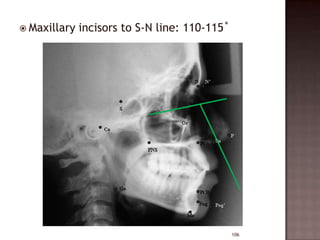

 Maxillary

incisors to S-N line: 110-115˚

106